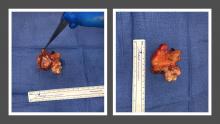

The pulmonary artery transection was completed and the pulmonary root was removed en bloc. Backtable inspection confirmed a 3.5 cm x 2.5 cm pedunculated mass with an anemone-like appearance and a stalk connected to the commissure of the anterior and left cusp.